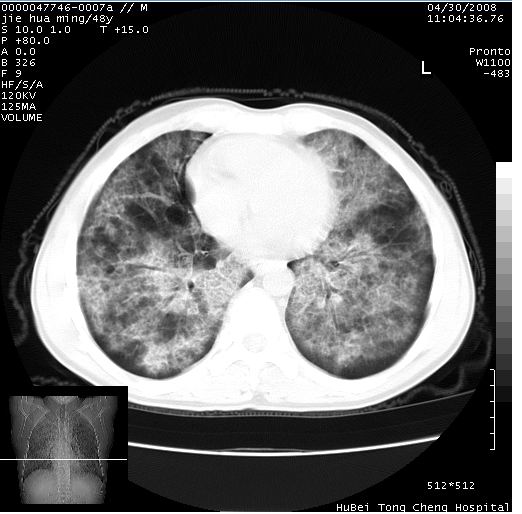

以下是引用dr.yang在2008-5-1 6:25:00的发言:[br]两肺广泛毛玻璃样的片状影,密度不均,边缘欠清,呈碎石路样改变,[br]考虑,1双肺间质性肺炎,2肺泡蛋白沉积症3支气管肺泡癌[br]

以下是引用hhcckk在2008-5-1 8:06:00的发言:[br]支持肺泡蛋白沉积症[br]依据:[br]1、病灶边缘清楚----地图征[br]2、病灶内部小叶间隔或小叶内间隔增厚所形成的网格状影----碎石路样表现[br]3、抗炎治疗无效(炎症抗炎治疗有效)[br]4、纵隔内未见肿大淋巴结(肺泡细胞癌时常有)[br][br]附肺泡蛋白沉积症资料[br][br]肺泡蛋白沉积症(pulmonary alveolar proteinosis)是一种原因不明的以肺泡腔内大量含脂糖蛋白样物质沉积为特征的疾病。[br]病理改变:(1)肺泡和细支气管腔内充满大量含脂糖蛋白样的粘稠物质,该物质为颗粒状或絮状的糖原pas染色阳性的磷脂蛋白。(2)肺泡壁及其间隔无异常改变。胸膜和淋巴结不受累及。(3)晚期可出现弥漫性肺间质纤维化。[br]临床表现:(1)好发年龄30~50岁,男性多于女性,偶见于儿童;(2)主要症状为呼吸困难、咳嗽、低热、消瘦、低氧血症和杵状指等。1/3的患者无症状。(3)实验室检查:痰液或肺泡灌洗液中可找到pas染色阳性颗粒物质。[br]hrct表现:肺泡蛋白沉积症具有特征性改变,即“碎石路样”表现(crazy-paving appearance,cpa)。主要包括(1)斑片状磨玻璃影:指肺野密度朦胧增加,内可见肺血管纹理影,系肺泡腔内充满低密度的磷脂蛋白物质所致。(2)其内部小叶间隔或小叶内间隔增厚所形成的网格状影,为小叶间隔水肿、肺泡壁内淋巴细胞和巨噬细胞浸润以及小叶内淋巴管扩张的缘故。(3)病灶边缘清楚,呈地图样分布于肺野外围或肺门及中央区。[br]

以下是引用zsl6918在2008-5-1 7:35:00的发言:[br]双肺磨玻璃样病变,可见铺碎路石征,病变区与正常区交错。边界清晰。符合肺泡蛋白质沉着征,高分辨扫描会更清楚漂亮。建议临床肺泡灌洗。

以下是引用yangyudong333在2008-5-1 5:36:00的发言:[br][br] 两肺广泛毛玻璃样的片状影,密度不均,边缘欠清,呈碎石路样改变,[br]考虑,1双肺间质性肺炎,2肺泡蛋白沉积症[br]